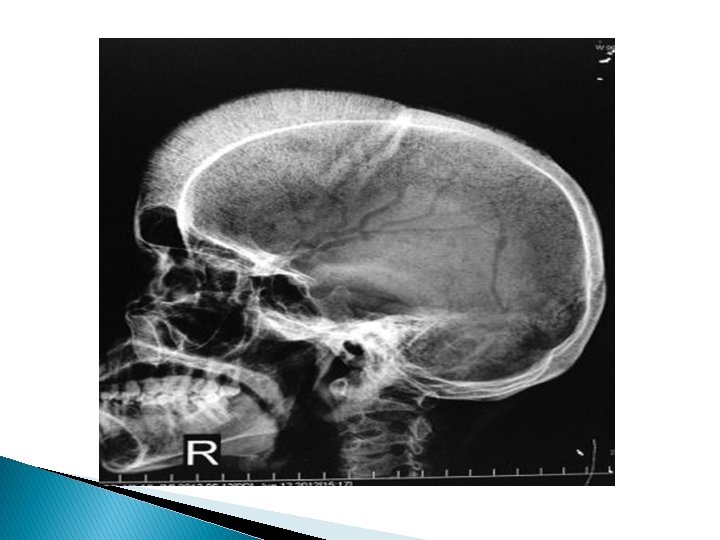

Examination v. General � � � ex : Pallor & jaundice No cyanosis Thalassemic facies ( frontal & parietal possing , prominent maxilla & exposure of upper central teeth ) v. Vital sings : � Pulse 120 b/min regular, normal vol & characters � B. P 90/60 mmhg on RT arm in sitting � R. R 20 c/min � Temp 37 c v. Anthropometric measurement � � Wt 16 kg Height 90 cm Hc 44 cm A. F closed :

Beta thalassemia major ( Cooley's anemia) : Clinical pictures onset in 2 nd half of 1 st year pallor , jaundice , hemosiderosis thalassemic facies hepatosplenomegaly growth retardation delayed puberty